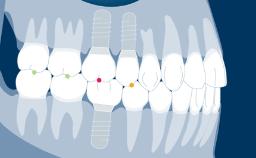

A second clinical image shows an example of an implant-supported single crown on the upper left central incisor where careful implant positioning has allowed the emergence profile to mimic that of the natural right central incisor.